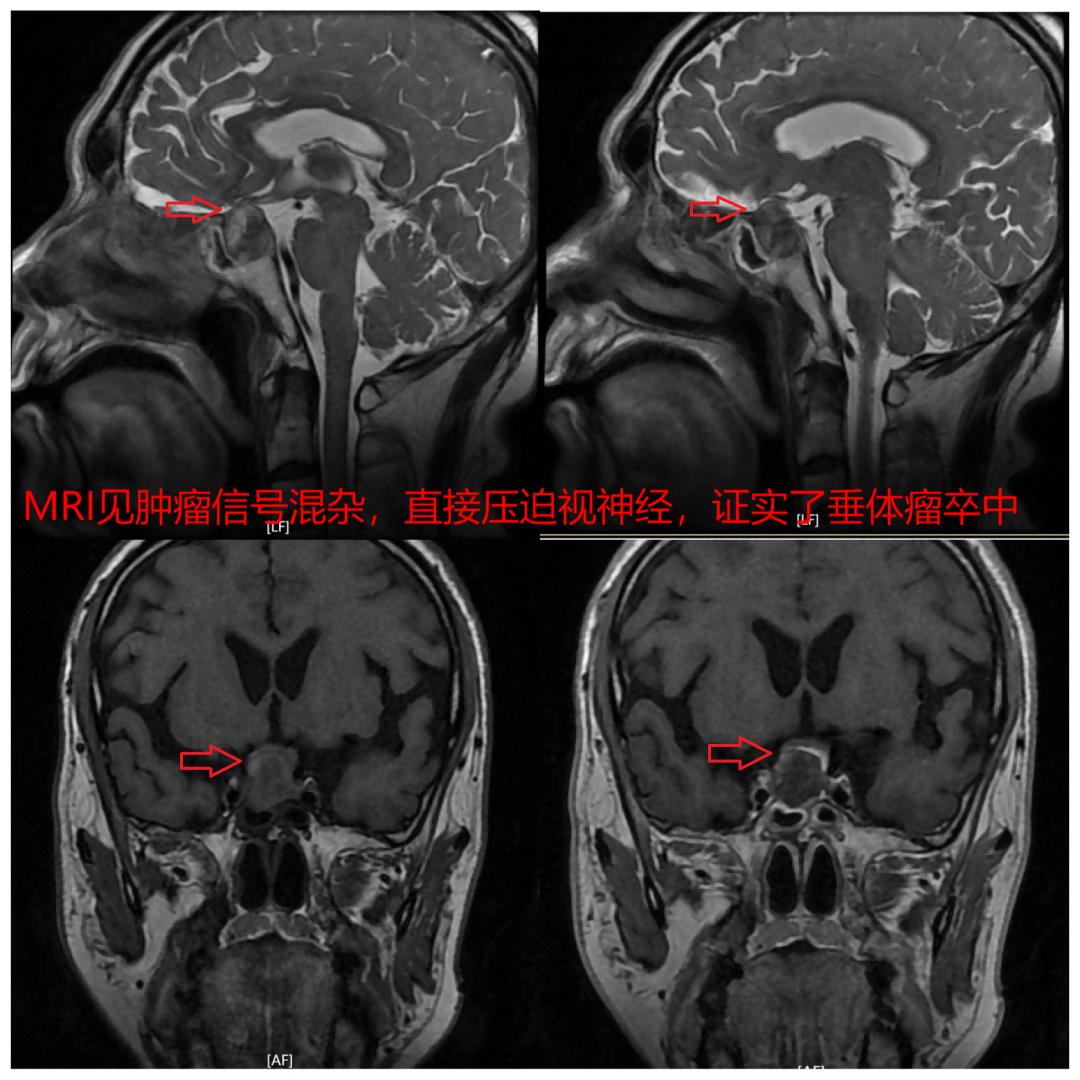

在急诊科、眼科、放射科和麻醉手术科等各科室的通力协作下,大爷很快收入院,并完成了必要的各项检查。影像学资料显示脑垂体瘤内混杂信号,体积明显增大,证实了脑垂体瘤卒中的诊断,而且肿瘤直接压迫了视交叉部分,尤其是右侧视神经,这正是右眼失明和左眼视力视野明显受损的病因。在完成了必要的激素和水电解质调整之后,在科主任顾英豪的指导下,由副主任医师赵浩主刀,副主任医师孙虎协同,紧急完成了全麻下神经内镜辅助经鼻蝶垂体腺瘤切除术。

通过追问病史,原来大爷半年前查体时就发现了垂体窝内有约直径1cm的阴影,但是由于没有任何症状,就没再继续到上级医院进一步诊疗。“所以这个基本上就能判定,是约1cm的脑垂体瘤突然出血体积明显增大,直径增大了1倍导致了头痛,而且直接压迫视神经的视交叉部分导致右眼的失明。”